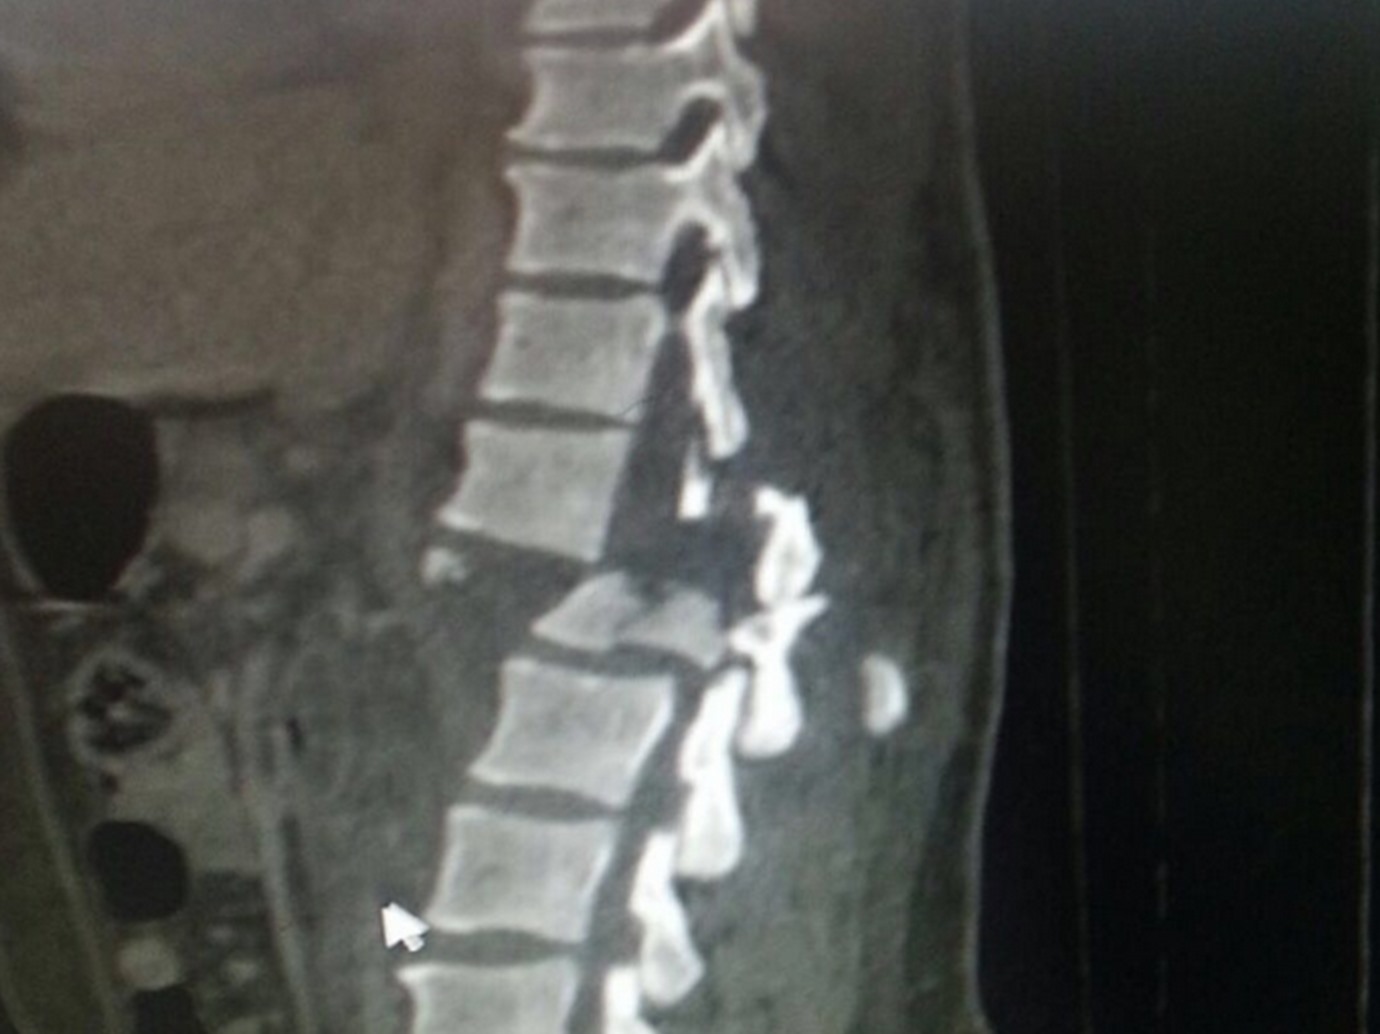

في حالة نادرة، تمكن فريق طبي بقسم العظام في مدينة الملك سعود الطبية، من تثبيت عمود فقري لمصاب تعرض للكسر في حادث مروري.

وقال رئيس قسم العظام بالمستشفى: إن العملية تكللت بالنجاح التام ولله الحمد، مضيفاً “أن شابا ثلاثينيا تعرض لحادث مروري نتج عنه إصابة بليغة في العمود الفقري، وهذه الحالة تعتبر نادرة عالمياً لما يتطلبه من وجود فريق طبي على مستوى عالٍ من الكفاءة والخبرة”.

وتابع: أن العملية استغرقت خمس ساعات، بقيادة استشاري جراحة العمود الفقري الدكتور معتصم عبيدات، والمريض الآن في تحسن مستمر ويستطيع مستقبلاً ممارسة حياته بشكل طبيعي.